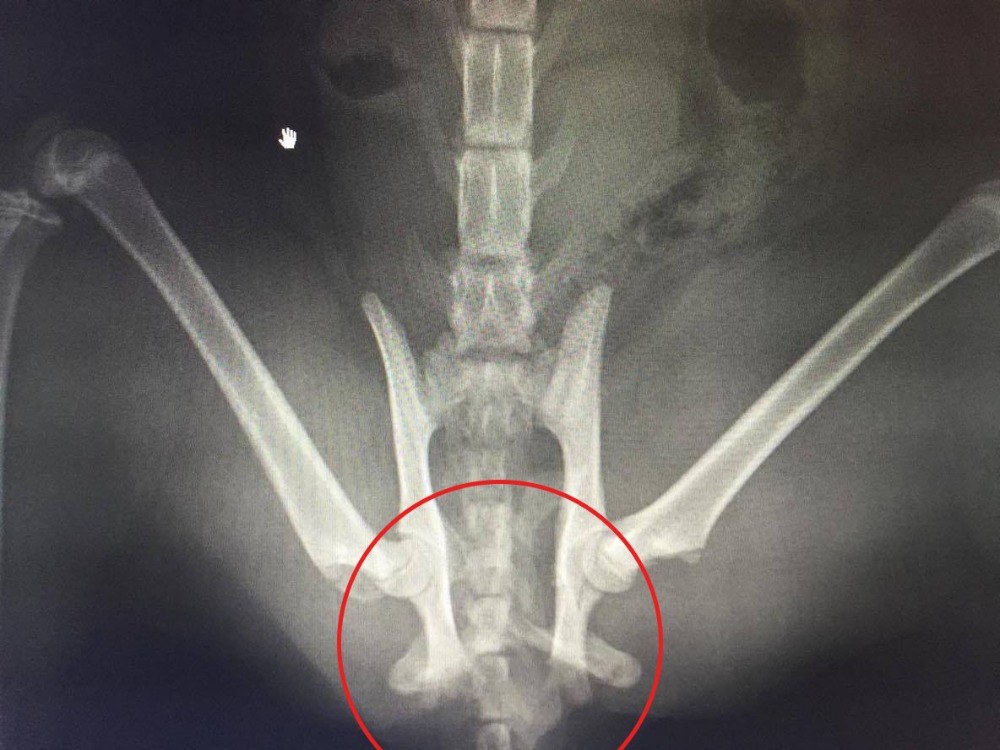

From haruna-oneday.com

[중재] 엉덩관절 골절(fracures of the hip) How Much Does It Cost To Fix A Cat's Broken Hip pelvic fracture repair for a cat might cost anywhere from $2,000 to $7,000 depending on the injuries and complexity of repair. Here, we break down how the total price can. according to a recent survey, the average cost of treating a broken cat leg is around $1000. if you think your cat might have a broken leg,. How Much Does It Cost To Fix A Cat's Broken Hip.